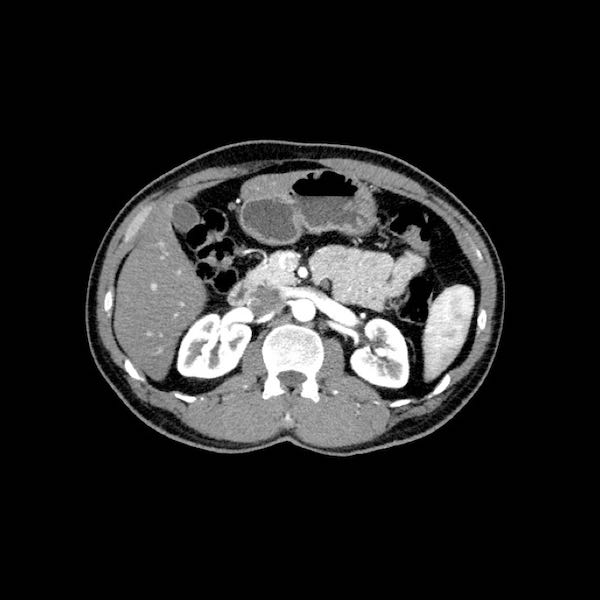

Tái tạo đa mặt phẳng vuông góc với tĩnh mạch cửa cho thấy mức độ tiếp xúc với tĩnh mạch cửa rộng hơn, từ 90 đến 180 độ (mũi tên).

Khi không có bất thường bờ viền, trường hợp này được phân loại là có thể cắt bỏ giới hạn (borderline resectable) theo tiêu chí DPCG, nhưng có thể cắt bỏ (resectable) theo tiêu chí NCCN.

Phẫu thuật cắt bỏ không kèm tái tạo tĩnh mạch cho kết quả R1, tức là có xâm lấn vi thể của khối u tại diện cắt.